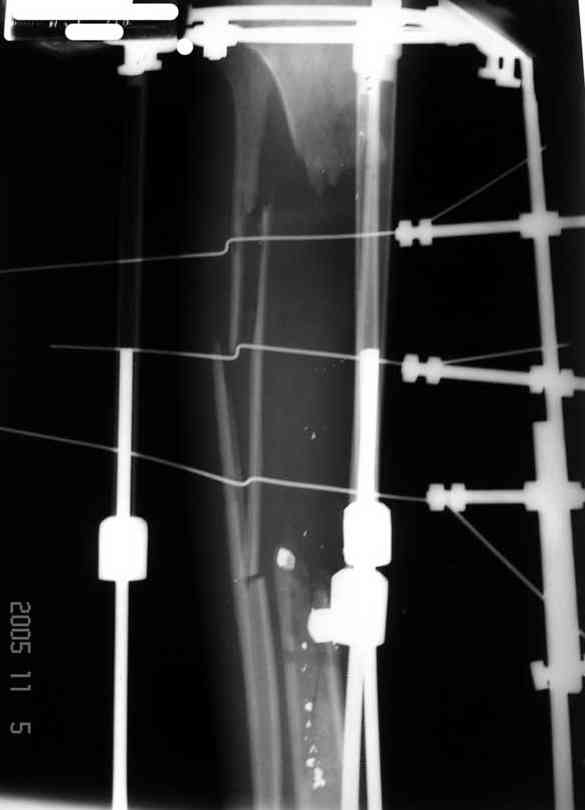

Реализовал описанную выше методику, и в итоге вот что получилось. Высылаю лишь прямые проекции,

в боковых тоже всё в тему.

Очень пригодились карбоновые кольца (Джолдас -огромное спасибо, я твой должник!!!), поскольку остеопороз дистального отломка был просто невероятный. На цифровом рентгене с трудом угадывались контуры.

Рентген в процессе перемещения - внизу карбоновые кольца, тракция фрагмента спицами с упором.

внешний вид в аппарате - не завершающем этапе, сначала стопа тоже была фиксирована в аппарате.

Сейчас аппарат сняли, но случай ещё не завершенный.

Признаюсь честно, не совсем уверен в прочности консолидации на стыке косточек. Кроме того, укорочение в районе 6 см. Сейчас реабилитация - ходит опираясь на ногу с одним костылем.